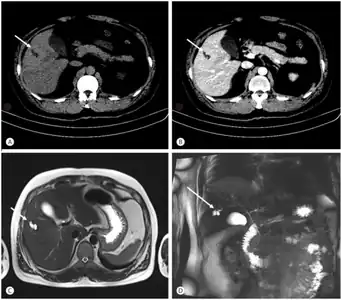

Turbo spin echo T2-weighted axial MRI of Caroli disease, showing cystic dilatations of bile ducts (shown as white).[1]

Modern imaging techniques allow the diagnosis to be made more easily and without invasive imaging of the biliary tree.[9] Commonly, the disease is limited to the left lobe of the liver. Images taken by CT scan, X-ray, or MRI show enlarged intrahepatic (in the liver) bile ducts due to ectasia. Using an ultrasound, tubular dilation of the bile ducts can be seen. On a CT scan, Caroli disease can be observed by noting the many fluid-filled, tubular structures extending to the liver.[4] A high-contrast CT must be used to distinguish the difference between stones and widened ducts. Bowel gas and digestive habits make it difficult to obtain a clear sonogram, so a CT scan is a good substitution. When the intrahepatic bile duct wall has protrusions, it is clearly seen as central dots or a linear streak.[10] Caroli disease is commonly diagnosed after this “central dot sign” is detected on a CT scan or ultrasound.[10] However, cholangiography is the best, and final, approach to show the enlarged bile ducts as a result of Caroli disease.